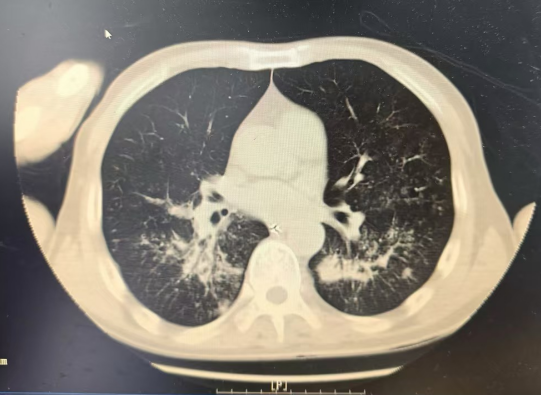

重症医学科林捷主任带领科室医护团队立即给予呼吸循环支持、容量管理、脏器功能保护等治疗,并进行床旁重症超声检查评估心肺功能等。抽血结果显示:血气分析提示氧合指数仅114mmHg(低于300提示存在呼吸衰竭),血乳酸3.49mmoL/L,白细胞高达20.9×109/L 。CT 提示:双肺大片炎症伴肺水肿。

治疗前CT影像